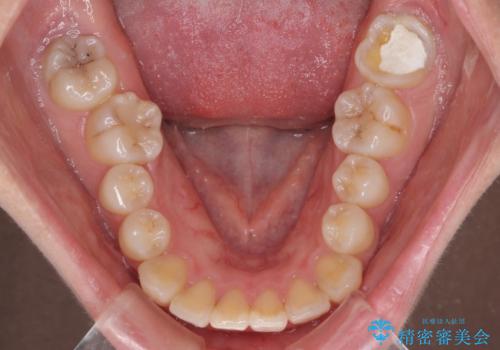

上下前歯がくちばしのように突出していましたが、抜歯矯正により口元が引っ込み、唇が閉じやすくなり、鼻の下の膨れた感じも解消されました。